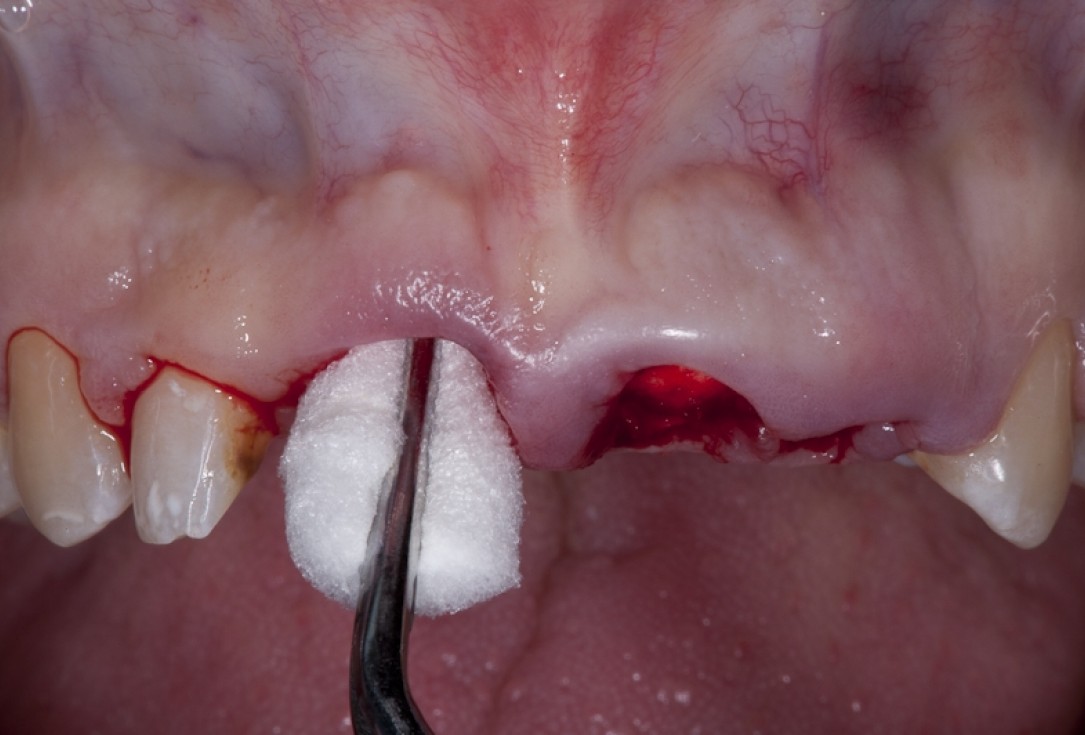

Socket preservation with permamem® - Dr. R. Rannula

Situation after tooth extraction.